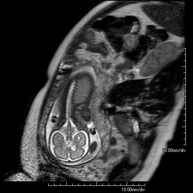

RM FetalProva diagnòstica no invasiva que consisteix en l'obtenció d'imatges d'alta definició anatòmica del fetus en la dona gestant mitjançant l'ús d'un camp electromagnètic i ones de ràdio (amb un emissor i un receptor). No utilitza radiació ionitzant. Es pot realitzar a partir de la dotzena setmana de gestació, essent segura tant per al fetus com per a la mare. S'utilitza si se sospita d'alguna anomalia congènita morfològica.